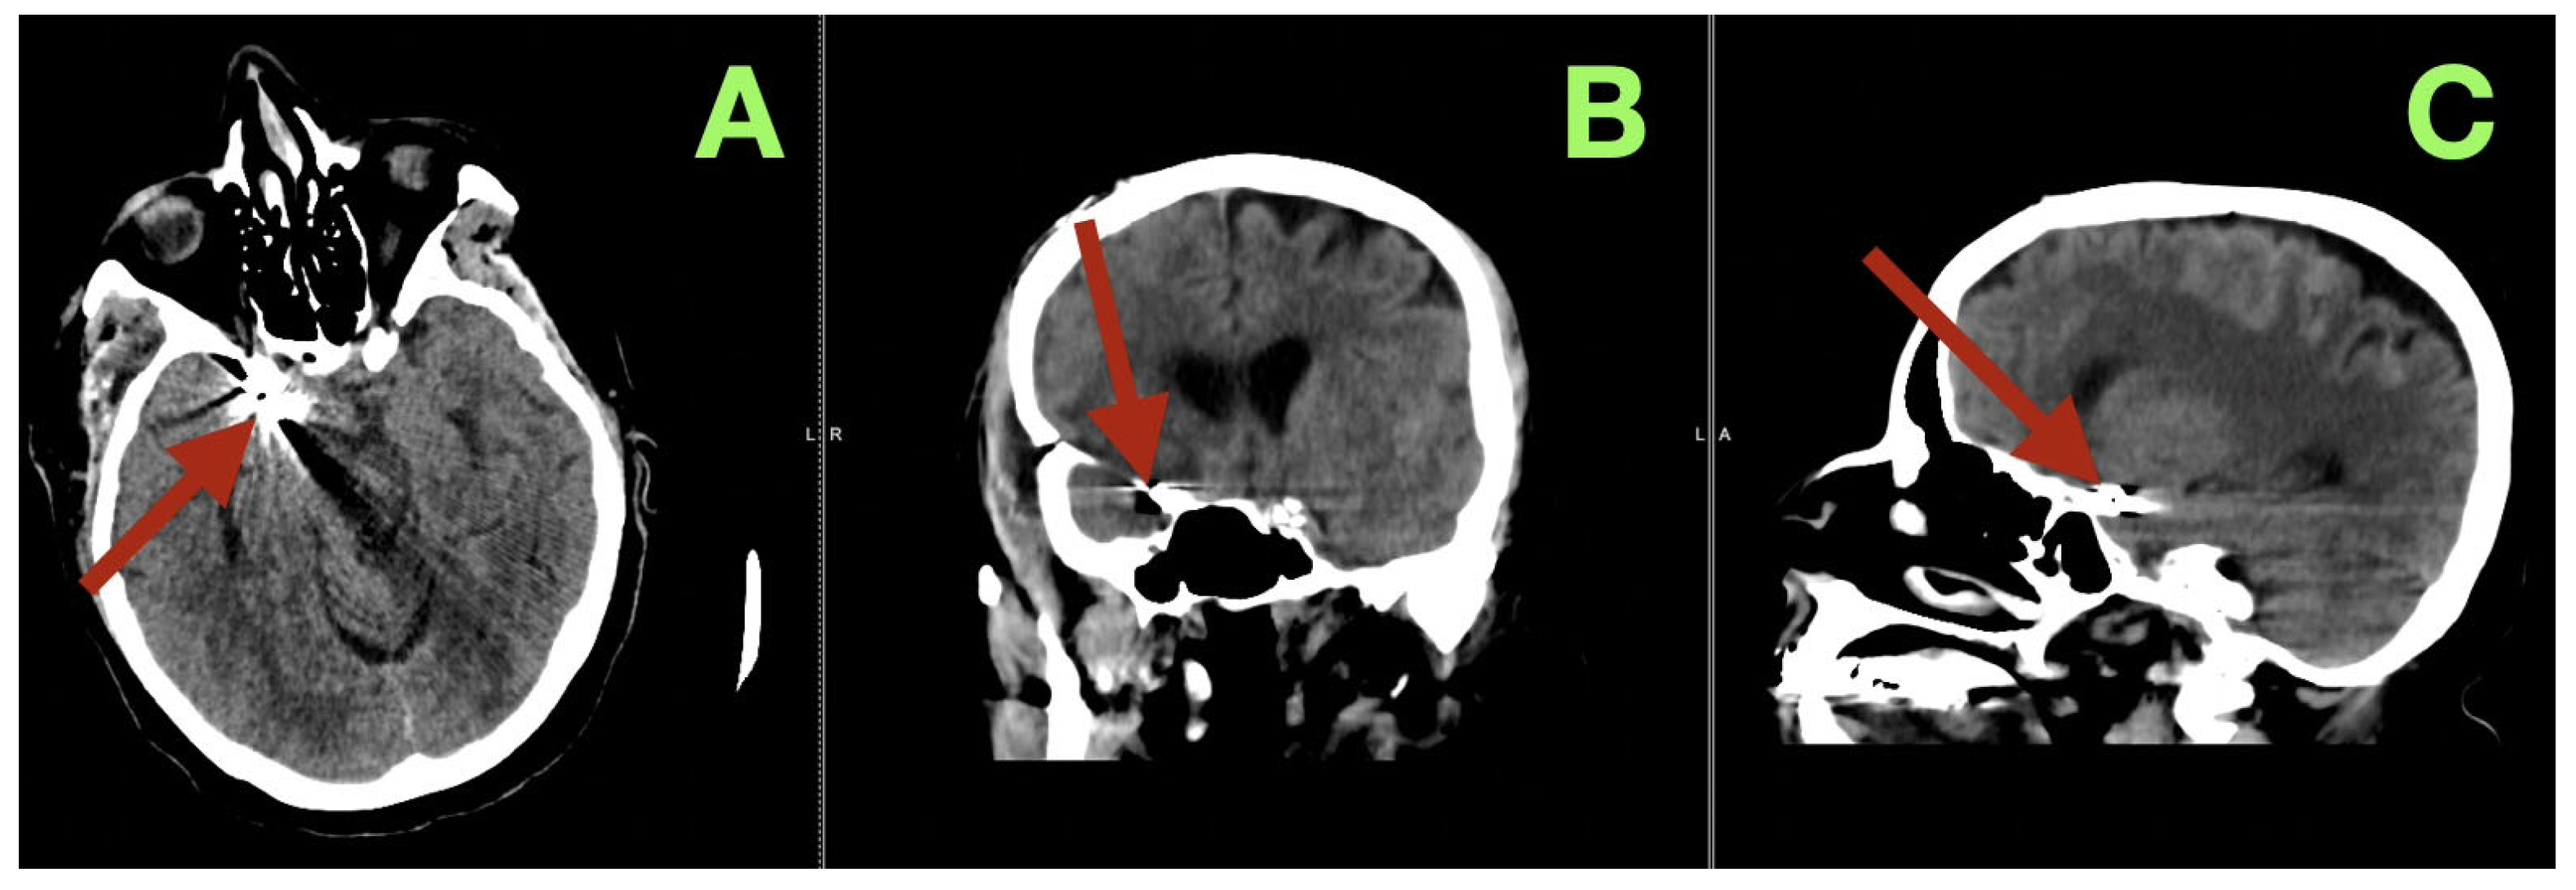

The first image obtained was a non-contrast cranial CT, which showed that there was an SAH (Fisher grade 4), hemorrhage into the ventricles of the brain, and generalized cerebral edema, along with evidence suggesting that the patient had acute hydrocephalus. Due to this verified hemorrhage pattern and significant risk of rebleeding, the patient underwent physiologic stabilization as part of the preoperative process; the patient was intubated and maintained a PaCO2 level between 35 and 38 mmHg to avoid hypercapnic related intracranial hypertension, and the patient’s arterial blood pressure was continuously monitored using nicardipine to keep the systolic blood pressure between 110 and 130 mmHg to decrease the risk of rebleeding while maintaining adequate cerebral perfusion. Selective right internal carotid artery angiography, including DSA, confirmed a saccular aneurysm located at the posterior communicating segment of the right internal carotid artery with a posteriorly oriented dome and a very narrow neck (<3 mm); the aneurysm arose from a branch critical area where a fetal type posterior cerebral artery (fPCA) branched off the aneurysm neck plane (Figure 1A–D). The presence of the aneurysm at a branch critical area made it necessary to reconstruct the junction of the aneurysm neck to the parent vessel, versus simply closing the aneurysm neck to preserve the lumen of the fPCA. Three-dimensional rotational angiography further defined the operative geometry and confirmed the aneurysm’s neck diameter to be approximately 2.5 mm and the maximum sac diameters to be approximately 7.7 × 6.6 mm (Figure 2C,D). The aneurysm was located at the carotid–PCom junction and was closely associated with the oculomotor cisternal corridor providing a potential anatomic basis for the intermittent pupillary variability observed during the acute phase of hemorrhage.

Figure 1.

Preoperative digital subtraction angiography (DSA). (A) Selective right internal carotid injection in a lateral projection demonstrates a posteriorly directed saccular aneurysm arising from the communicating segment (arrow), seated at the carotid–posterior communicating region. (B) Oblique projection confirms posterior dome projection (arrow) and refines the profile of the aneurysm base at the junctional complex. (C) Complementary lateral/oblique acquisition delineates the compact neck architecture (arrow), supporting a focal saccular morphology rather than fusiform dilation. (D) Anteroposterior projection provides orthogonal confirmation of lesion position (arrow) at the right carotid communicating segment, validating neck definition and dome directionality across planes.